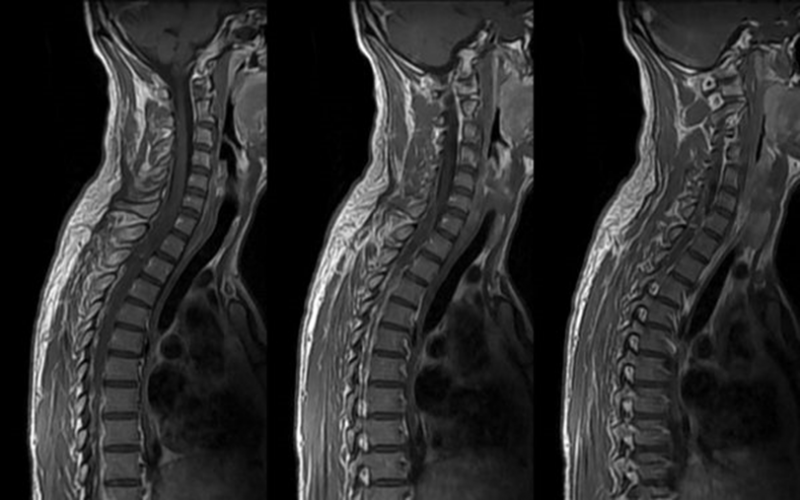

ЯКІ ВИГИНИ ХРЕБТА ВИ БАЧИТЕ НА РЕНТГЕНОГРАМІ?

варіанти відповідей

ЦЕРВІКАЛЬНИЙ ЛОРДОЗ, ТОРАКАЛЬНИЙ КІФОЗ

ТОРАКАЛЬНИЙ КІФОЗ

ЦЕРВІКАЛЬНИЙ ЛОРДОЗ